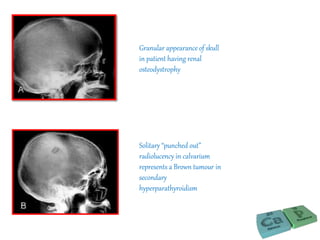

Granular appearance of skull

in patient having renal

osteodystrophy

Solitary “punched out”

radiolucency in calvarium

represents a Brown tumour in

secondary

hyperparathyroidism